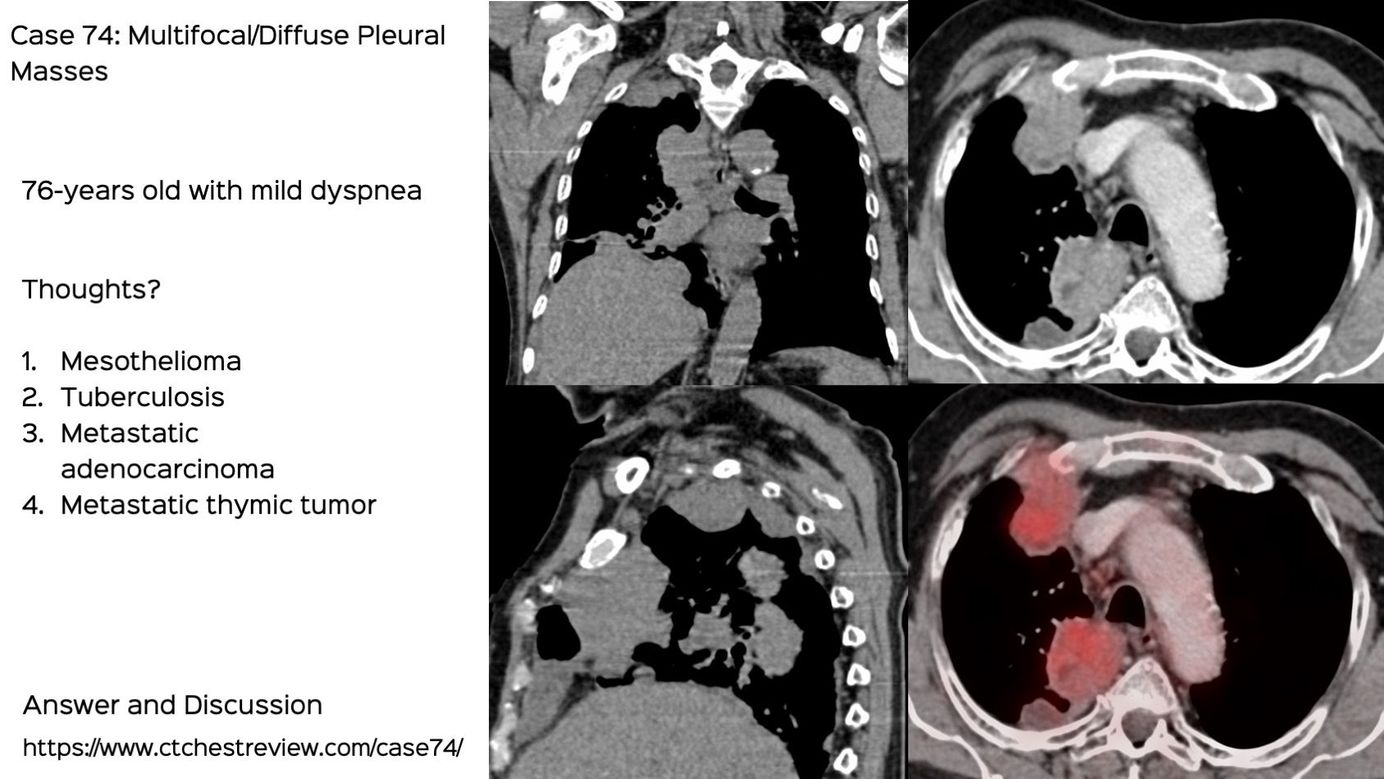

Case 74: Multifocal / Diffuse Pleural Disease Members Public

Multifocal / diffuse pleural masses have a short differential diagnosis